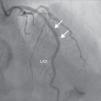

A 69-year-old man was referred for PCI of a 90% calcified lesion in the mid left anterior descending artery (LAD) involving the second diagonal branch (D2; Figure 1, arrow). After the left coronary ostium was cannulated and crossed with two BMW® wires, one to the LAD and other to the D2, predilation with a 2.5 mm×15 mm Trek® balloon was performed and an unsuccessful attempt was made to cross the stenosis with a 2.75 mm×22 mm Resolute Integrity® drug-eluting stent. Predilation was repeated with a 2.75 mm×15 mm Trek® non-compliant balloon at high pressure. Suddenly, balloon rupture was detected and the angiogram showed LAD rupture with extensive contrast extravasation into the pericardium (Figure 2, arrows; Video 1). Protamine sulfate was used to reverse the effect of heparin and the drug-eluting stent was deployed with balloon inflation for 10 minutes to seal the type III perforation but, as dye extravasation persisted, a 3.0 mm×19 mm GraftMaster® covered stent was superimposed, followed by rapid cessation of contrast leakage (Video 2). The D2 branch was lost (Figure 3, arrows), and periprocedural myocardial infarction occurred. The final image showed pericardial effusion (Figure 4; Video 3). The echocardiogram excluded tamponade. Forty-eight hours later, atrial fibrillation occurred with hemodynamic deterioration. Pericardiocentesis was performed and 50 ml of serosanguineous fluid was drained. Sinus rhythm was restored, with favorable evolution thereafter.